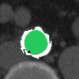

At this point, the dataset is ready for the processing in the portal ImageLab. The latter, takes as input the basal ROI and its corresponding CM one, together with their respective binary masks. These, are used by the algorithm to create the image (see Fig. 2), and consequently to detect the vessel. As depicted in Fig. 4, in output the extracted image is provided, along with a colored map where green highlights pixels correctly classified by the algorithm, red indicates misclassified ones, and white indicates the areas the algorithm should have identified but did not. Adjacent to this, similarity indices described before are presented, computed by considering the CM image as the target, which is provided as input for this purpose. We have processed in the portal each slice of our dataset.